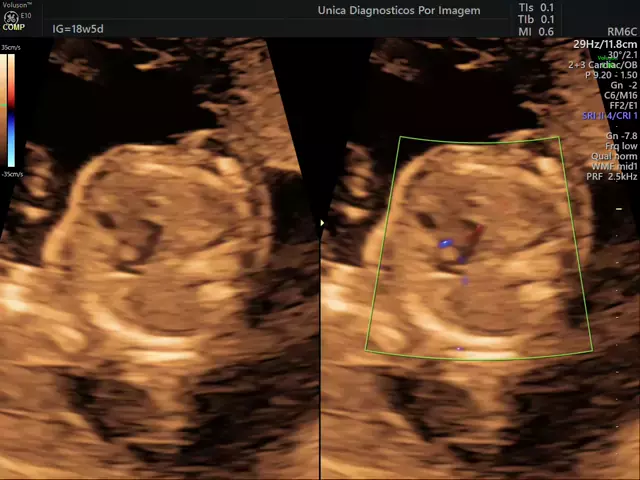

ultrassom 4D obstetrico.

Doppler..